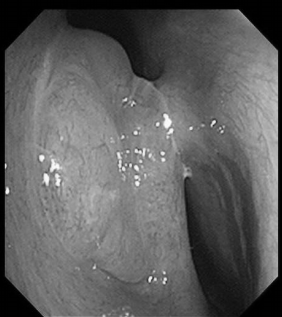

电子喉镜检查:鼻息肉(双)